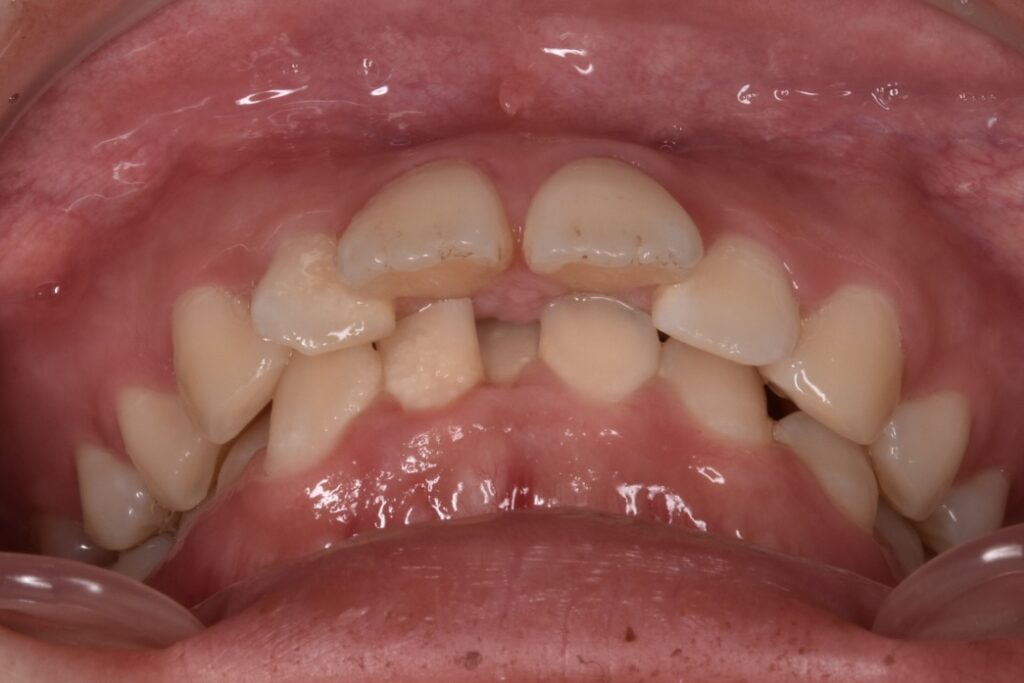

治療前